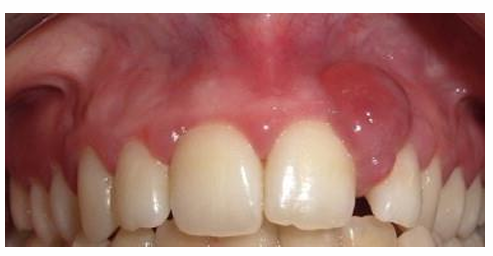

MFD EXAMS /23 6 1234567891011121314151617181920212223 You have 30 min to complete this exam. The timer will start once you begin Attention: Only a few minutes left! Please submit your answers soon. MFD 1 Get a quick sneak peek before the real exam !This trial quiz is designed to show you the question style, difficulty level, and how the options will appear on the platform. 1 / 23 1. What is the lethal dose and toxic dose of fluoride, management? Check 2 / 23 2. What the advantage of silver diamine over other methods and disadvantages ? Check 3 / 23 3. Method of topical fluoride application with concentration ? Check 4 / 23 4. What will happen if left untreated? Check 5 / 23 5. What changes that will happen if the habit stopped? Check 6 / 23 6. Give 3 of your initial stage of treatment? Check 7 / 23 7. What are the causes? Check 8 / 23 8. What is this? Check 9 / 23 9. Then they specified the type of pain and asked about the diagnosis Check 10 / 23 10. What other tests to check vitality of the pulp? Check 11 / 23 11. What are the factors will govern the Rx of Posterior cross bite ? Check 12 / 23 12. What are the factors that govern the treatment of anterior cross bite? Check 13 / 23 13. Name the appliance that you can use to treat this case? Check 14 / 23 14. Name 3 causes? Check 15 / 23 15. Name the most important clinical diagnostic information you need to know. (check RCSI intensive course )? Check 16 / 23 16. What do you see? Check 17 / 23 17. What is your treatment? Check 18 / 23 18. Name the investigations needed? Check 19 / 23 19. causes for gingival enlargement ? Check 20 / 23 20. What is the common side effect of this drug? Check 21 / 23 21. Name the drug that he may take to treat this condition? Check 22 / 23 22. The patient may have what? Check 23 / 23 23. What is this clinical condition? Check /31 2 12345678910111213141516171819202122232425262728293031 You have 30 min to complete this exam. The timer will start once you begin Attention: Only a few minutes left! Please submit your answers soon. MFD 2 Get a quick sneak peek before the real exam !This trial quiz is designed to show you the question style, difficulty level, and how the options will appear on the platform. 1 / 31 1. Mention 2 fixed space maintainers and 2 removable space maintainers other from mentioned : Check 2 / 31 2. Other space maintenance used for child lost primary second molar E before the eruption of the permanent molars ? Check 3 / 31 3. What are the difference between nance appliance and Transpalatal arch Check 4 / 31 4. What material used to attach band? Check 5 / 31 5. What instruction you give to patient? Check 6 / 31 6. Name other fixed space maintainer used in upper jaw and mechanism of their action? Check 7 / 31 7. What component of this appliance? Check 8 / 31 8. What is this appliance , for what its used ? Check 9 / 31 9. Treatment? Check 10 / 31 10. Define Abrasion and Erosion? Check 11 / 31 11. What does this picture show? Check 12 / 31 12. what investigations you can do ? Check 13 / 31 13. Drugs can lead to lichenoid reaction Check 14 / 31 14. What extra oral features in “ Lichenoid reaction )? Check 15 / 31 15. What microscopical features of it ( licheonoid reaction )? Check 16 / 31 16. Definitive diagnosis ? Check 17 / 31 17. Mention type of suggested biopsy ? Check 18 / 31 18. Mention 4 differential diagnosis ? Check 19 / 31 19. Mention 4 questions you will ask the patient ? Check 20 / 31 20. Give 4 intraoral decription of what you see ? Check 21 / 31 21. What the other surgery can be performed to make prothesis? Check 22 / 31 22. Can this tooth stand with fixed prothesis? (in the opg )à taken from Malek file ? Check 23 / 31 23. Radiograph of missing multiple teeth consider it according to Antes law? ON which tooth you will make Abutment ? Check 24 / 31 24. What is Antes law? Check 25 / 31 25. What is best one to use as abutment in fixed prosthesis A or B? Check 26 / 31 26. What relevance of this picture? Check 27 / 31 27. What’s complication of doing surgery in this area floor of mouth? Check 28 / 31 28. Other 2 radiograph needed in diagnosis? Check 29 / 31 29. Give 4 differential diagnosis? Check 30 / 31 30. What can you see ? Check 31 / 31 31. What is the name of radiograph? Check Your score is /30 1 123456789101112131415161718192021222324252627282930 You have 30 min to complete this exam. The timer will start once you begin Attention: Only a few minutes left! Please submit your answers soon. MFD 3 Get a quick sneak peek before the real exam !This trial quiz is designed to show you the question style, difficulty level, and how the options will appear on the platform. 1 / 30 1. Treatment? Check 2 / 30 2. Histopathology? Check 3 / 30 3. Differential diagnosis Check 4 / 30 4. Clinical features’? Check 5 / 30 5. Patient said, this lesion is very frequent, why? Check 6 / 30 6. What are the causes for ulcers? Check 7 / 30 7. Patient have other signs like uveitis ,Genital ulcerations which syndrome he had ? Check 8 / 30 8. Name of the lesion ? Check 9 / 30 9. Mention some TMJ movement ? Check 10 / 30 10. Blood supply ? Check 11 / 30 11. Nerve supply ? Check 12 / 30 12. Which muscles close? Check 13 / 30 13. Action of open and open wide? Check 14 / 30 14. Why it’s Atypical joint ? Check 15 / 30 15. Name of the ligaments ? Check 16 / 30 16. What would be your management? Check 17 / 30 17. Bacteria involved Check 18 / 30 18. Which type of Periodontitis? Check 19 / 30 19. Treatment? Check 20 / 30 20. Histopathology? Check 21 / 30 21. Differential diagnosis? Check 22 / 30 22. Clinical features? Check 23 / 30 23. What are the time frames for making a complaint? Check 24 / 30 24. What are the 3 points related to negligence? Check 25 / 30 25. Who is allowed access to the patient records? Check 26 / 30 26. How to differentiate if it is upper or lower motor neuron lesion? Check 27 / 30 27. Management? Check 28 / 30 28. What are the causes? Check 29 / 30 29. What should you advise the patient to do? Check 30 / 30 30. What is this lesion? Check Your score is /24 1 123456789101112131415161718192021222324 You have 30 min to complete this exam. The timer will start once you begin Attention: Only a few minutes left! Please submit your answers soon. MFD 4 Get a quick sneak peek before the real exam !This trial quiz is designed to show you the question style, difficulty level, and how the options will appear on the platform. 1 / 24 1. What does MRONJ stands for? Check 2 / 24 2. Give definition for MRONJ Check 3 / 24 3. For what medical problems these medications are used? Check 4 / 24 4. Stages of MRONJ 3 Check 5 / 24 5. What’s this appliance? Check 6 / 24 6. At what age is it used? Check 7 / 24 7. What type of malocclusion is it used to treat? Check 8 / 24 8. What changes will produce? (4 options) Check 9 / 24 9. Disadvantages? Check 10 / 24 10. Why is it flabby tissue? Check 11 / 24 11. what is this condition called? Check 12 / 24 12. Causes ? Check 13 / 24 13. Clinical Features ? Check 14 / 24 14. How to avoid it ? Check 15 / 24 15. Management? Check 16 / 24 16. Ideal post length and width Check 17 / 24 17. Definition of Ferrule it’s the Check 18 / 24 18. What is the importance of the ferrule effect ? Check 19 / 24 19. Describe the radiolucency? Check 20 / 24 20. Give 6 differential diagnosis? Check 21 / 24 21. Give 5 radiographical features? Check 22 / 24 22. What is the difference between incisional and excisional biopsy? Check 23 / 24 23. What other 2 plain radiographs we can we can take? Check 24 / 24 24. ALARA? Check Your score is /22 1 12345678910111213141516171819202122 You have 30 min to complete this exam. The timer will start once you begin Attention: Only a few minutes left! Please submit your answers soon. MFD 5 Get a quick sneak peek before the real exam !This trial quiz is designed to show you the question style, difficulty level, and how the options will appear on the platform. 1 / 22 1. . Types of external root resorption? Check 2 / 22 2. The cause of root resorption in the pic? Check 3 / 22 3. How you will treat it? Check 4 / 22 4. What is this probe? Check 5 / 22 5. What is the mark a ? Check 6 / 22 6. What is the mark b ? Check 7 / 22 7. What is the score from the given reading? Check 8 / 22 8. What is the treatment need of the patient according to the score? Check 9 / 22 9. What is the differential diagnosis ? Check 10 / 22 10. Four clinical features of the lesion? Check 11 / 22 11. Treatment ? Check 12 / 22 12. Describe what do you see? Check 13 / 22 13. Causes for it ? Check 14 / 22 14. Treatment ? Check 15 / 22 15. Picture of patient with Anaphylaxis…after taking Check 16 / 22 16. What is diagnosis? - Check 17 / 22 17. What a the signs of Anaphyalxis reactions ? Check 18 / 22 18. What first line of treatment? Dose? Route of Adminstration? Check 19 / 22 19. Other drug used? Check 20 / 22 20. What are expected complications if not treated ? Check 21 / 22 21. What precautions should be made to prevent anaphylaxis reaction ? - Check 22 / 22 22. Name 10 drug in emergency used with their route of Administration and their condition they use in? Check Your score is /36 1 123456789101112131415161718192021222324252627282930313233343536 You have 30 min to complete this exam. The timer will start once you begin Attention: Only a few minutes left! Please submit your answers soon. MFD 6 Get a quick sneak peek before the real exam !This trial quiz is designed to show you the question style, difficulty level, and how the options will appear on the platform. 1 / 36 1. . What are cases that you have to extract the primary tooth? Check 2 / 36 2. D. What are the indications for extraction? Check 3 / 36 3. What are your treatment options? Check 4 / 36 4. Investigations? Check 5 / 36 5. Type of trauma? Check 6 / 36 6. Patient diagnosed with sjorgen syndrome Histology ? - Check 7 / 36 7. Patient diagnosed with sjorgen syndrome Mention four blood investigations ? Check 8 / 36 8. Patient diagnosed with sjorgen syndrome Mention two sites where can we take the biopsy Check 9 / 36 9. Patient diagnosed with sjorgen syndrome How can you differentiate between primary and secondary ? Check 10 / 36 10. Gingival inflammation present in which syndrome Check 11 / 36 11. What is the treatment? Check 12 / 36 12. mention another connective tissue disease that can lead to lesions “ intraorally “ similar to the Lichen planus ? Check 13 / 36 13. what serious complication can arise from Erosive lichen planus ? Check 14 / 36 14. If it was atrophic lesion what histology might be seen ? Check 15 / 36 15. List the histological features of lichen planus ? Check 16 / 36 16. Lichen planus what dose it affect? Check 17 / 36 17. Age group commonly affected ? -ref SAQ Check 18 / 36 18. What are the clinical presentation ‘ types of lichen planus ‘ Check 19 / 36 19. What might you see in patient’s body that has a relation to this lesion? Check 20 / 36 20. What are the differential diagnoses? Check 21 / 36 21. Factors for platelet adhesion? Check 22 / 36 22. What can you see? Check 23 / 36 23. Other 2 process of hemostasis? Check 24 / 36 24. Two diseases in which they increase ? Check 25 / 36 25. Two diseases in which they decrease? Check 26 / 36 26. Medical term when they decrease? And if they increased Check 27 / 36 27. Function Check 28 / 36 28. Life span ? Check 29 / 36 29. From where they arise? Check 30 / 36 30. Normal number? Check 31 / 36 31. What are the function of the guiding plane ? Check 32 / 36 32. The success rate ? Check 33 / 36 33. Mention single extra preparation requirement for Resin bonded bridge in posterior teeth ? Check 34 / 36 34. Mention 5 preparation features of it? Check 35 / 36 35. Give two advantages of it ? Check 36 / 36 36. What’s the name of this prosthesis? Check Your score is /23 1 1234567891011121314151617181920212223 You have 30 min to complete this exam. The timer will start once you begin Attention: Only a few minutes left! Please submit your answers soon. MFD 7 Get a quick sneak peek before the real exam !This trial quiz is designed to show you the question style, difficulty level, and how the options will appear on the platform. 1 / 23 1. If the same scenario but the tooth is subluxated. What is the management? Check 2 / 23 2. Aim of this procedure Check 3 / 23 3. Steps to do this procedure? Check 4 / 23 4. Management? How to asses the vitality of the tooth Check 5 / 23 5. Mention factors that can affect the treatment plan ? Check 6 / 23 6. Identify the Kenneyd’s classification Check 7 / 23 7. Name its parts? Check 8 / 23 8. Uses of Surveyor Check 9 / 23 9. What is this ? Check 10 / 23 10. Criteria for hand piece sterilization Check 11 / 23 11. steps for wrapped instrument sterilization process ( ref : sterilization in SDCEP)? Check 12 / 23 12. What is the difference between sterilization and decontamination? Check 13 / 23 13. Optimal temperature & pressure & time for autoclave? Check 14 / 23 14. Difference between vacuum and non-vacuum autoclave in mechanism? Check 15 / 23 15. Optimum temperature? Check 16 / 23 16. Advantage of vaccum over non vaccum? Check 17 / 23 17. What is the significance of forehead wrinkling? Check 18 / 23 18. What is Ramsy haunt syndrome ? Rx ? and is it LMN or UMN ? Check 19 / 23 19. Enumerate 3 extracranial and intracranial causes for this ? Check 20 / 23 20. What are the branches of facial nerve? Check 21 / 23 21. Why do we suture the eye in a patient with Facial Palsy? Check 22 / 23 22. Differentiate between Upper and Lower Motor Neuron lesions? Check 23 / 23 23. What is shown in photograph? Check Your score is /27 0 123456789101112131415161718192021222324252627 You have 30 min to complete this exam. The timer will start once you begin Attention: Only a few minutes left! Please submit your answers soon. MFD 8 Get a quick sneak peek before the real exam !This trial quiz is designed to show you the question style, difficulty level, and how the options will appear on the platform. 1 / 27 1. Mention 4 diseases you would see in HIV Patients? Check 2 / 27 2. Give 2 differential diagnosis for this lesion? Check 3 / 27 3. Describe the lesion shown in Photograph B? Check 4 / 27 4. What is your diagnosis ? Check 5 / 27 5. Describe the lesion shown in Photograph A? Check 6 / 27 6. Disadvantages of gold ? Check 7 / 27 7. Ideal cement for All Porcelain? Check 8 / 27 8. Which cement would u use for high caries risk patient? Check 9 / 27 9. How much would you prepare for functional and non-functional cusps in Gold Crown? Check 10 / 27 10. what crown would you go for in bruxism patients out of these 3? Check 11 / 27 11. Name the 3 restorations? Check 12 / 27 12. After administering Local Anesthesia and deciding the choice of biopsy. What should be done before biopsying the lesion? Check 13 / 27 13. Name 2 systemic steroids with dosage you would recommend for this patient? Check 14 / 27 14. Name 2 topical steroids with dosage you would recommend for this patient? Check 15 / 27 15. What is your diagnosis? Check 16 / 27 16. Describe the lesion shown in photograph? Check 17 / 27 17. Name 5 options to increase retention and stability in class l Check 18 / 27 18. E. What is the function of the RPI system ? Check 19 / 27 19. What are the 2 disadvantages of the 2 restorations you mentioned? Check 20 / 27 20. What materials are your 2 restorations made of? Check 21 / 27 21. Other than implants what restoration would you place in this patient? Check 22 / 27 22. Which Kennedy’s classification is this? Check 23 / 27 23. Describe your management? Check 24 / 27 24. What may be the patient complaint? Check 25 / 27 25. What are the causes of this? Check 26 / 27 26. Describe what you see in the photograph? Check 27 / 27 27. which 4 examinations would you undertake? Check Your score is /31 0 12345678910111213141516171819202122232425262728293031 You have 30 min to complete this exam. The timer will start once you begin Attention: Only a few minutes left! Please submit your answers soon. MFD 9 Get a quick sneak peek before the real exam !This trial quiz is designed to show you the question style, difficulty level, and how the options will appear on the platform. 1 / 31 1. Describe what you see in the photograph? Check 2 / 31 2. Three other features of this syndrome ? Check 3 / 31 3. What is the medical condition associated with it “? Multiple OKC? Check 4 / 31 4. Where expansion occurs in the OKC ? Check 5 / 31 5. From which cells this lesion arises from? Check 6 / 31 6. What is your diagnosis? Check 7 / 31 7. What is the histopathology of the lesion shown in Histology slide? Check 8 / 31 8. Give 4 differential diagnosis? Check 9 / 31 9. What is the consequence of premature loss of deciduous teeth? Check 10 / 31 10. Identify those appliances and mention one use for each and mode of action? Check 11 / 31 11. What component of appliance no. 3 ? Check 12 / 31 12. How to overcome open bite disadvantage ? Check 13 / 31 13. What are Disadvantages of this appliance ? Check 14 / 31 14. What Ceph changes are expected while using this appliance ? Check 15 / 31 15. What is the construction of Twin Block Appliance? Check 16 / 31 16. What skeletal and dental changes are expected while using this appliance ? Check 17 / 31 17. What is the ideal age to treat this condition >? Check 18 / 31 18. Indications of the Twin Block Appliance? Two Check 19 / 31 19. Name the Appliance used to correct this? Check 20 / 31 20. What is the treatment? Check 21 / 31 21. How to prevent it Check 22 / 31 22. Mention three mechanisms of action of Fluoride? Check 23 / 31 23. What is the disease caused by excess Fluoride? Check 24 / 31 24. What are the risk factors associated with this patient? Check 25 / 31 25. Name the principal organism causing this? Check 26 / 31 26. what are the principles of the access cavity Check 27 / 31 27. What is your diagnosis? Check 28 / 31 28. What are principles of cavity preparation? Check 29 / 31 29. What is your Periapical diagnosis? Check 30 / 31 30. What is your Pulpal diagnosis? Check 31 / 31 31. Which test would you undertake? Check Your score is /21 0 123456789101112131415161718192021 You have 30 min to complete this exam. The timer will start once you begin Attention: Only a few minutes left! Please submit your answers soon. MFD 10 Get a quick sneak peek before the real exam !This trial quiz is designed to show you the question style, difficulty level, and how the options will appear on the platform. 1 / 21 1. Patient is 20 years old Mention two treatment options for this case ? Check 2 / 21 2. Patient is 20 years old What is the long term risk for not treating this case ? Check 3 / 21 3. Name of this appliance in the next picture? Check 4 / 21 4. What is the wire used ? Check 5 / 21 5. For which orthodontic cases this appliance is necessary ? Check 6 / 21 6. Why we use retainer ? Check 7 / 21 7. Describe what you see ? Check 8 / 21 8. Differential diagnosis:- Check 9 / 21 9. Name of those muscles ? Check 10 / 21 10. Name the Extrinsic muscles of the tongue? Check 11 / 21 11. . Which nerves innervate the Extrinsic muscles of the tongue?. Check 12 / 21 12. What is the somatic innervation of anterior 2/3 of tongue? Check 13 / 21 13. Which nerve supplies the posterior 1/3 of tongue?. Check 14 / 21 14. From which Pharyngeal arch posterior 1/3 derived from? Check 15 / 21 15. Mention the intrinsic muscle of the tongue ? Check 16 / 21 16. What is the name of this condition ? name the lesion on the skin ? Check 17 / 21 17. Mention 3 drugs that causing it ? Check 18 / 21 18. 2 infections associated with it Check 19 / 21 19. Mention 2 immediate treatment ? Check 20 / 21 20. Why this condition can be fatal ? Check 21 / 21 21. Which test would you undertake? Check Your score is